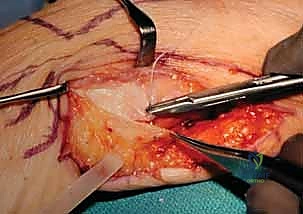

With the ulnar diaphysis resected, the ulnar head is now freely mobile, tethered only by the TFCC and ulnocarpal ligaments distally. We use a sturdy towel clip or a small bone clamp to grasp the ulnar head. By applying gentle traction and rotating the head, we gain excellent access to the articular surfaces of the DRUJ.

Using a high-speed burr or a sharp rongeur, we meticulously decorticate the articular cartilage down to bleeding subchondral bone on both the ulnar head and the corresponding sigmoid notch of the radius. It is absolutely critical during this step to protect the distal and volar attachments of the TFCC to the fovea of the ulnar head. Stripping these attachments will